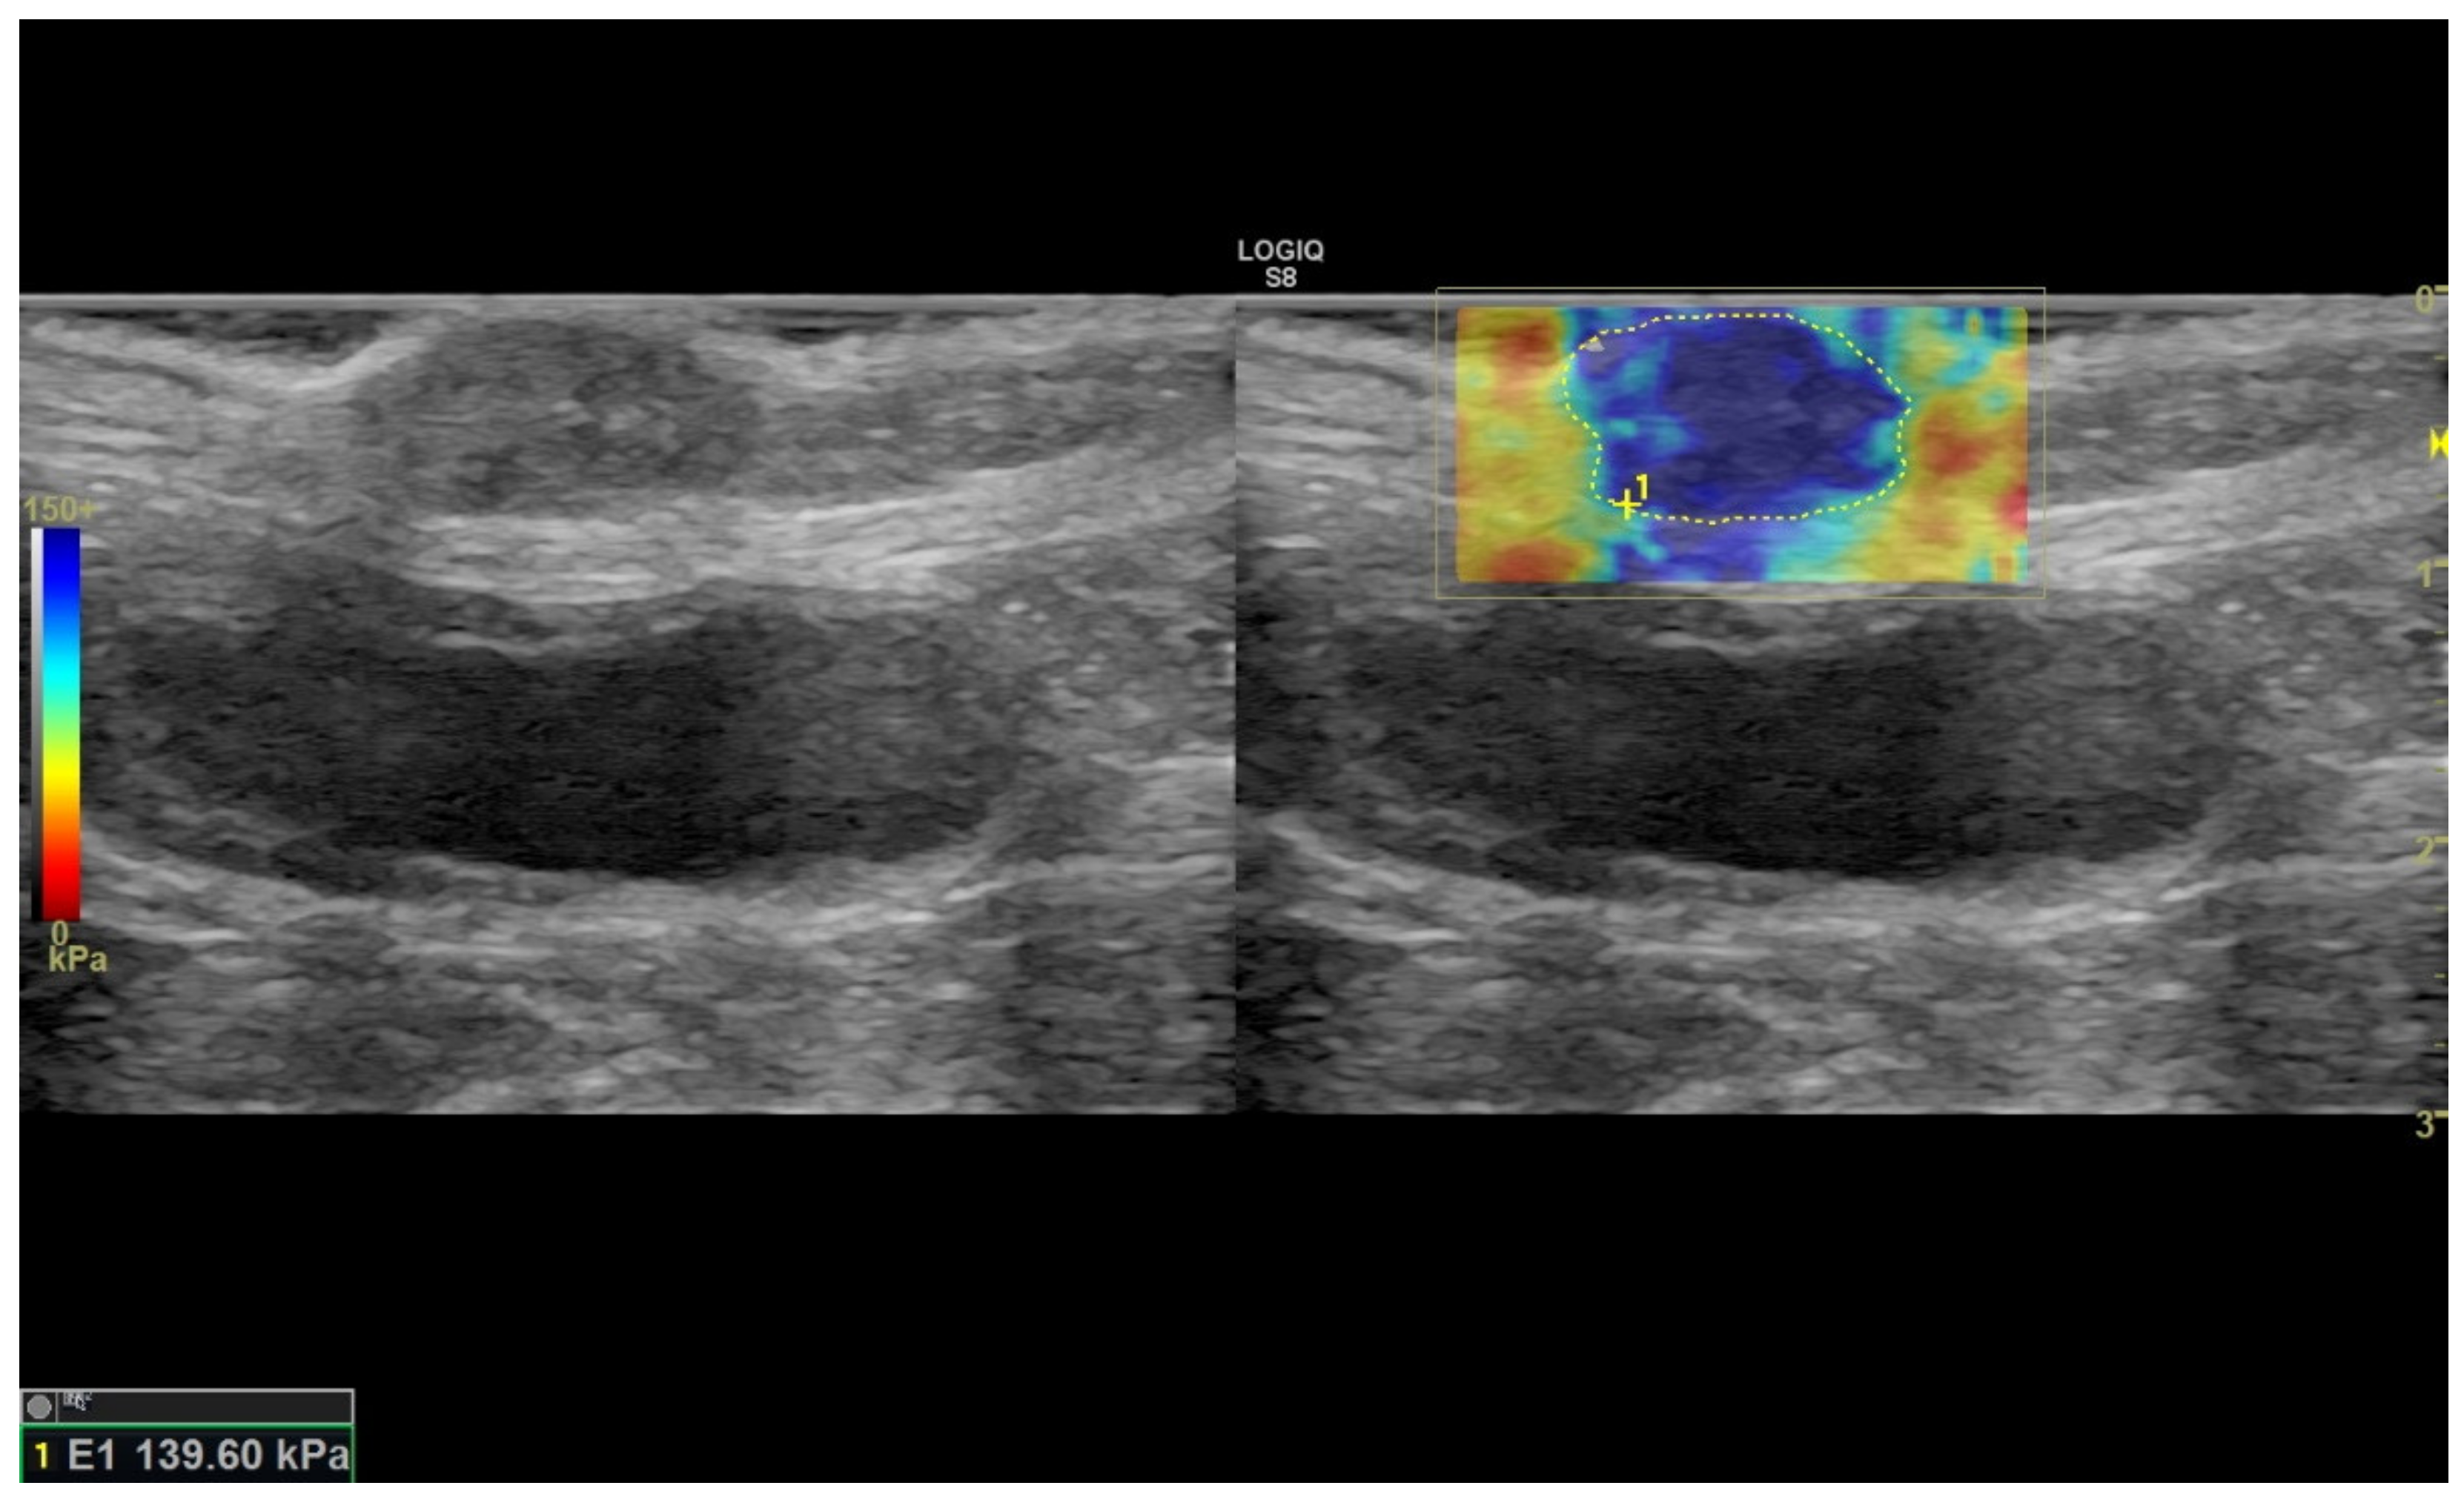

2.2. Ultrasound Sonoelastography

3.1. Sonoelastography and Correlation between Elastographic Parameters